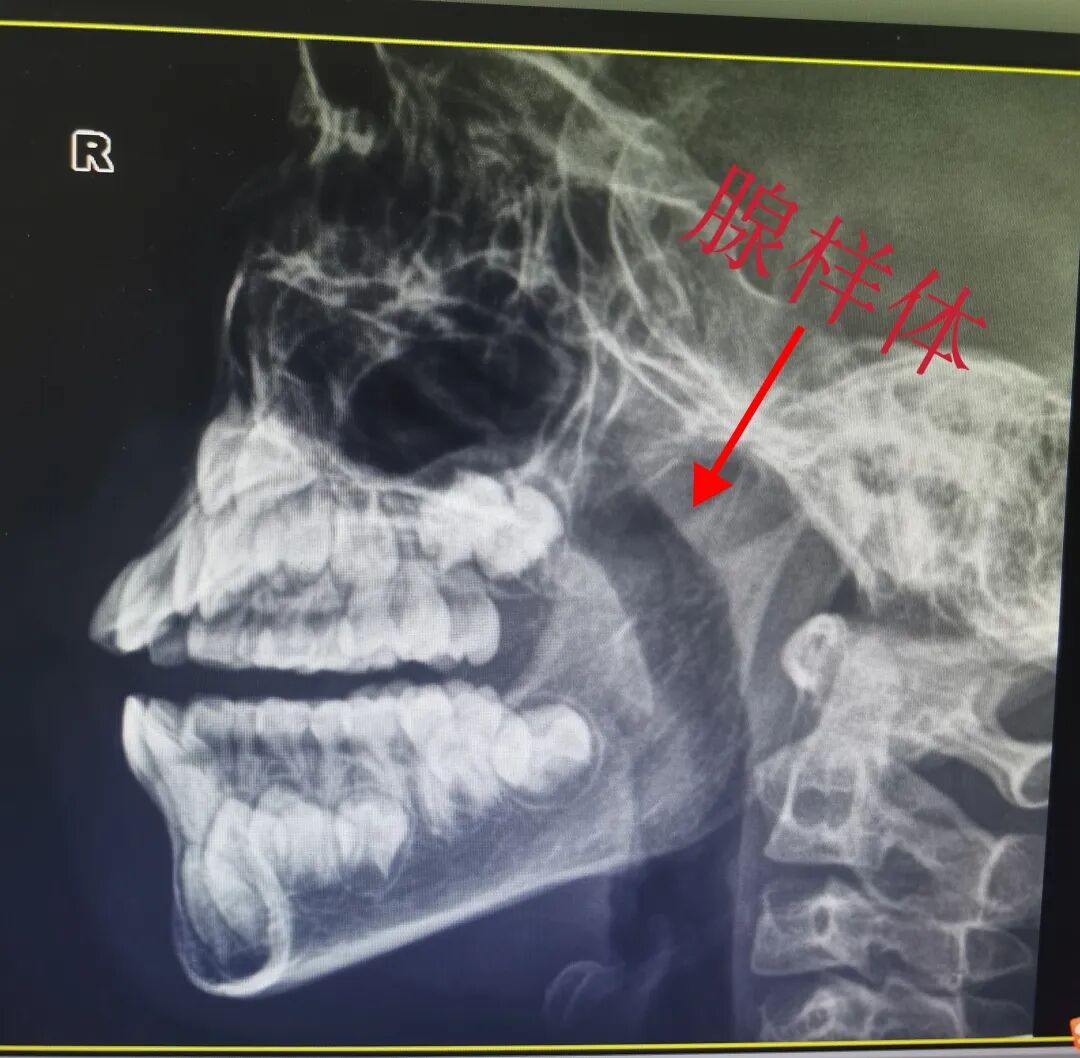

药物治疗配合微波治疗一月后

可以看出患儿的腺样体缩小了,气道变宽了。